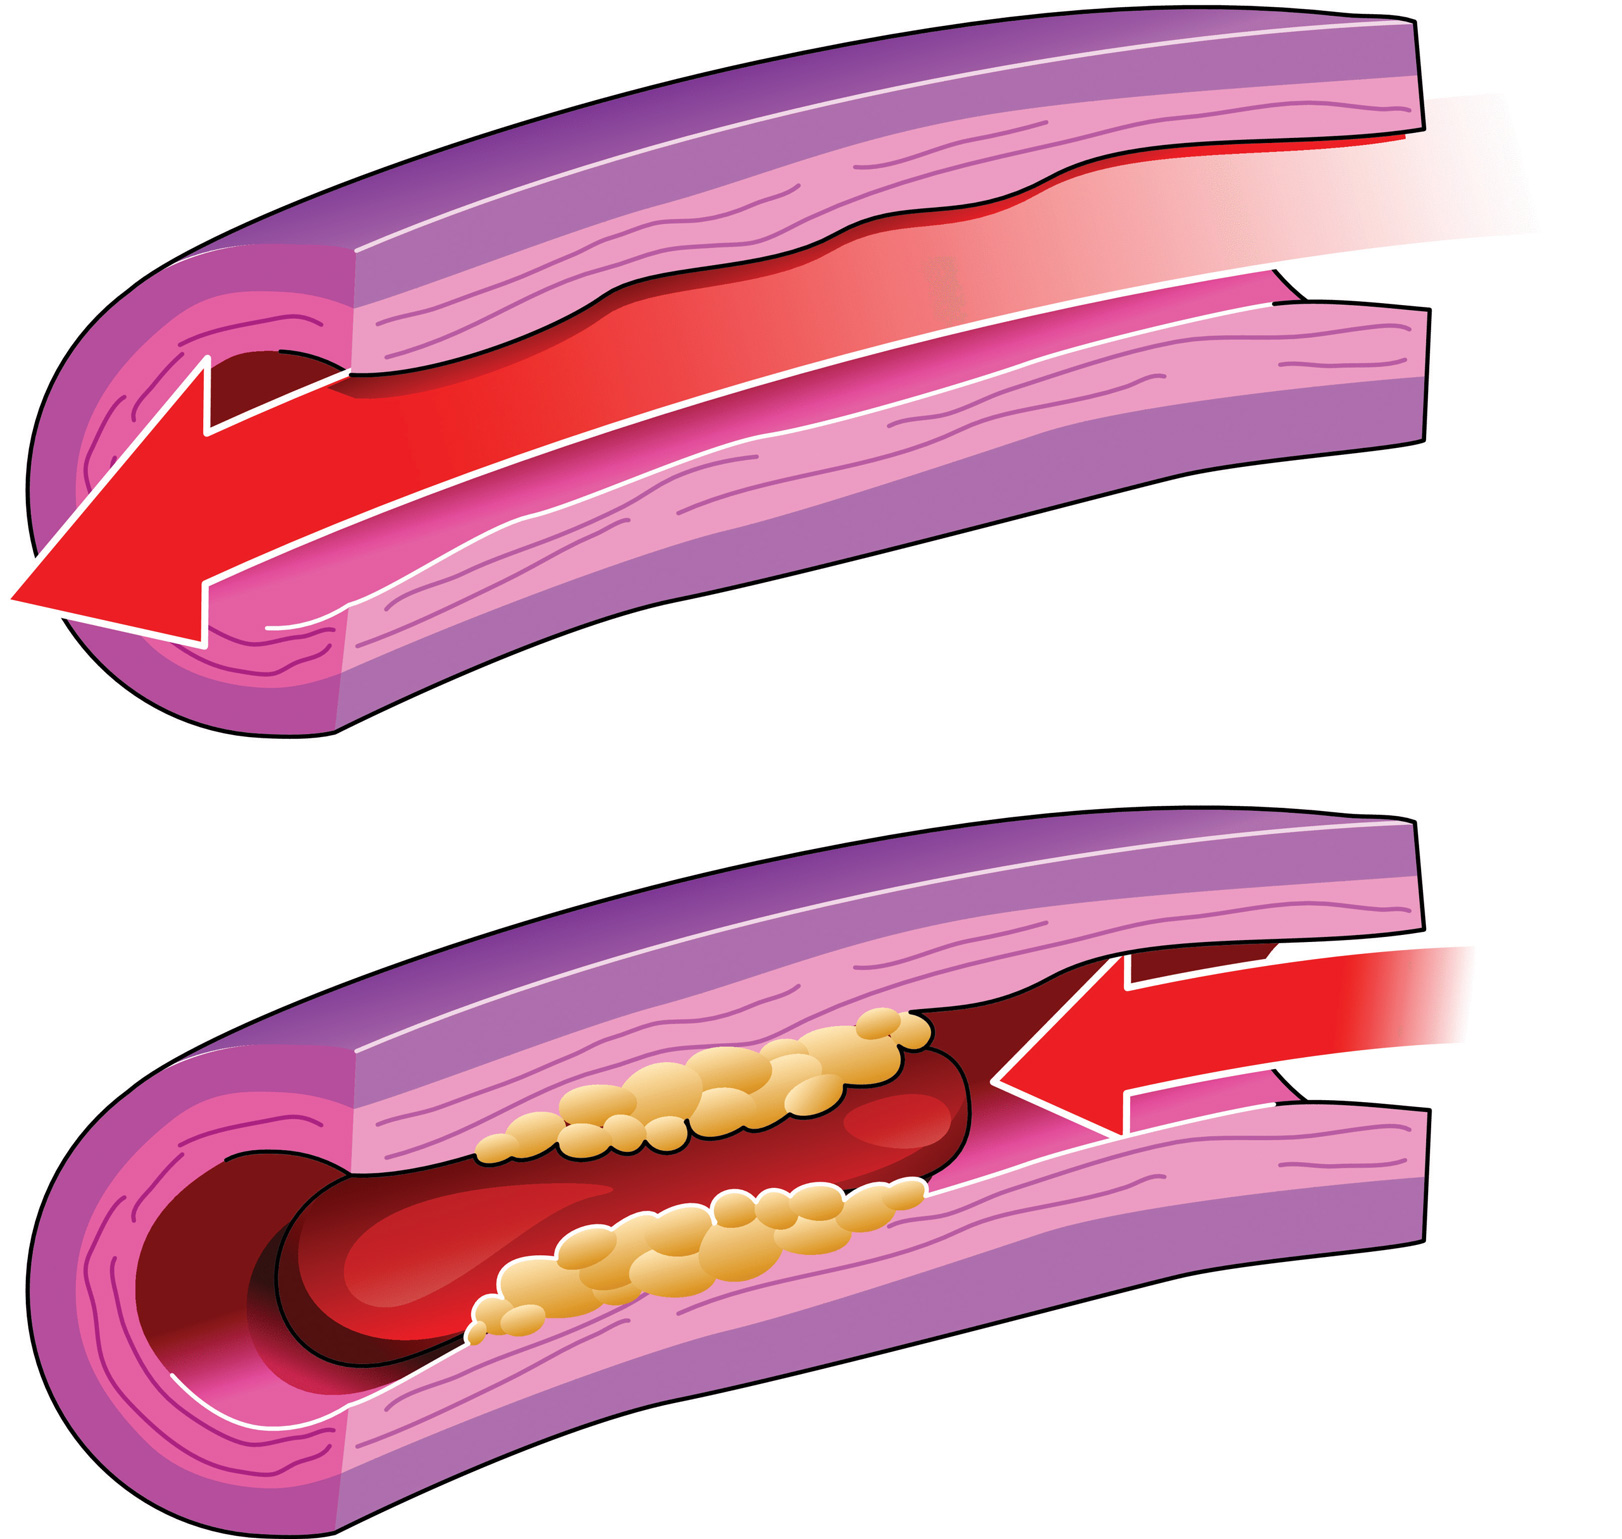

A typical blood vessel. ( a ) shows a normal artery with normal blood …

Normal Artery And Unhealthy Artery Stock Vector – Image: 52223409

Artery Blockage caused by Plaque – TrialExhibits Inc.